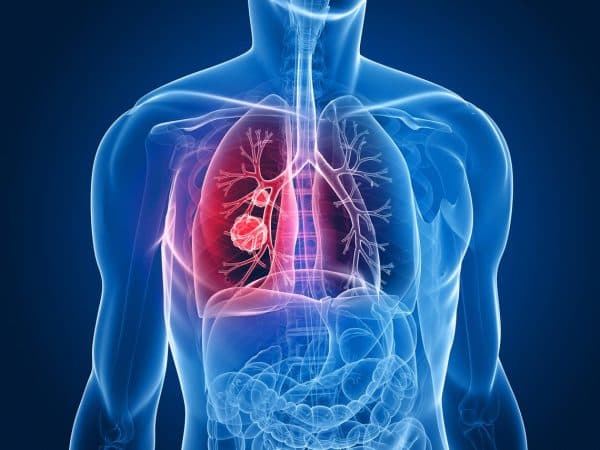

Áp xe phổi do biến chứng viêm phổi

Khi trẻ bị viêm phổi nhưng không được điều trị tốt, gây viêm mủ và hoại tử vùng nhu mô phổi bị tổn thương, khiến cơ chế thanh thải bị suy yếu, gây hiện tượng thuyên tắc hoặc vi trùng lan theo đường máu hình thành nên khối áp-xe phổi. Khối áp xe có hình dạng một hang tròn có bờ rõ, thành dày trong phổi, bên trong có chứ dịch mủ.

Khi thăm khám thấy lồng ngực di động giảm, giảm phế âm, gõ đục, ran ẩm và tiếng thổi ống. Chụp X-quang ngực có thể phát hiện một ổ mủ đơn độc, thành dày trong phổi có hoặc không có mức khí dịch.